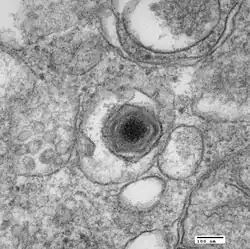

Electron micrograph of a virus particle

ASFV is a large (175–215 nm), icosahedral, double-stranded DNA virus with a linear genome of 189 kilobases containing more than 180 genes.[6] The number of genes differs slightly among different isolates of the virus.[7] ASFV has similarities to the other large DNA viruses, e.g., poxvirus, iridovirus, and mimivirus. In common with other viral hemorrhagic fevers, the main target cells for replication are those of monocyte, macrophage lineage. Entry of the virus into the host cell is receptor-mediated, but the precise mechanism of endocytosis is presently unclear.[8]

Macrophage cell in early stages of infection with ASFV

Assembly of the icosahedral capsid occurs on modified membranes from the endoplasmic reticulum. Products from proteolytically processed polyproteins form the core shell between the internal membrane and the nucleoprotein core. An additional outer membrane is gained as particles bud from the plasma membrane. The virus encodes proteins that inhibit signalling pathways in infected macrophages and thus modulate transcriptional activation of immune response genes. In addition, the virus encodes proteins which inhibit apoptosis of infected cells to facilitate production of progeny virions. Viral membrane proteins with similarity to cellular adhesion proteins modulate interaction of virus-infected cells and extracellular virions with host components.[1]